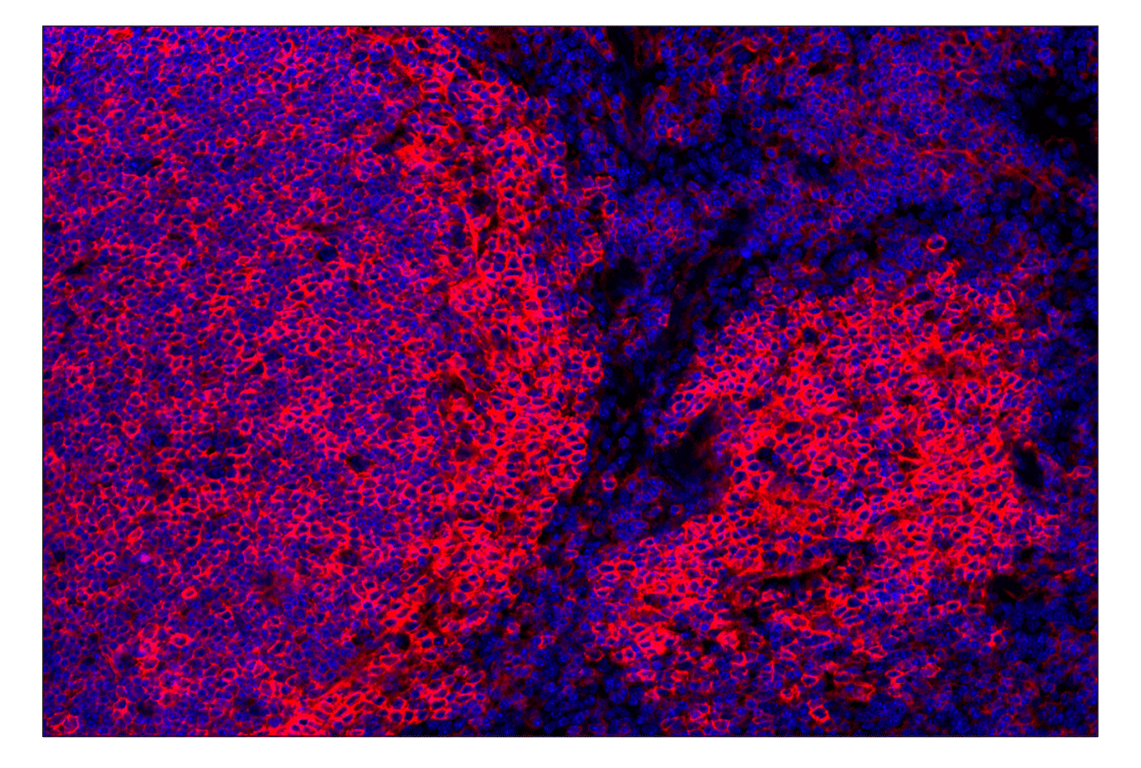

CD38 (E9F5A) Rabbit Monoclonal Antibody (Alexa Fluor® 555 Conjugate) #52005

Immunohistochemistry (Paraffin) 1:100 - 1:400

CD38 (E9F5A) Rabbit Monoclonal Antibody (Alexa Fluor® 555 Conjugate) recognizes endogenous levels of total CD38 protein.